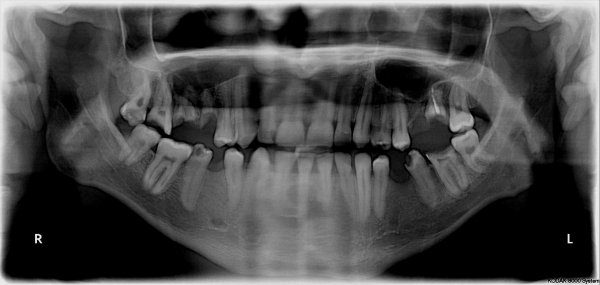

Добрый день. Мне в стоматологии сделали снимок зуба и сказали, что зуб надо удалять, так как вылечить не получится. Подскажите, так ли это? Может стоит обратиться к другим врачам? (фото зуба выслала на e-mail). Зуб № 46. На данный момент зуб не беспокоит. Три месяца назад был флюс, после разреза всё прошло. Антибиотиками не лечила, так как беременность. Сейчас срок 17 недель. Спасибо!

Да, к сожалению зуб необходимо удалить, так как на верхушках всех корней наблюдается обширное воспаление.